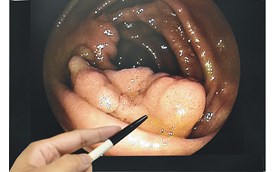

內視鏡縮胃手術